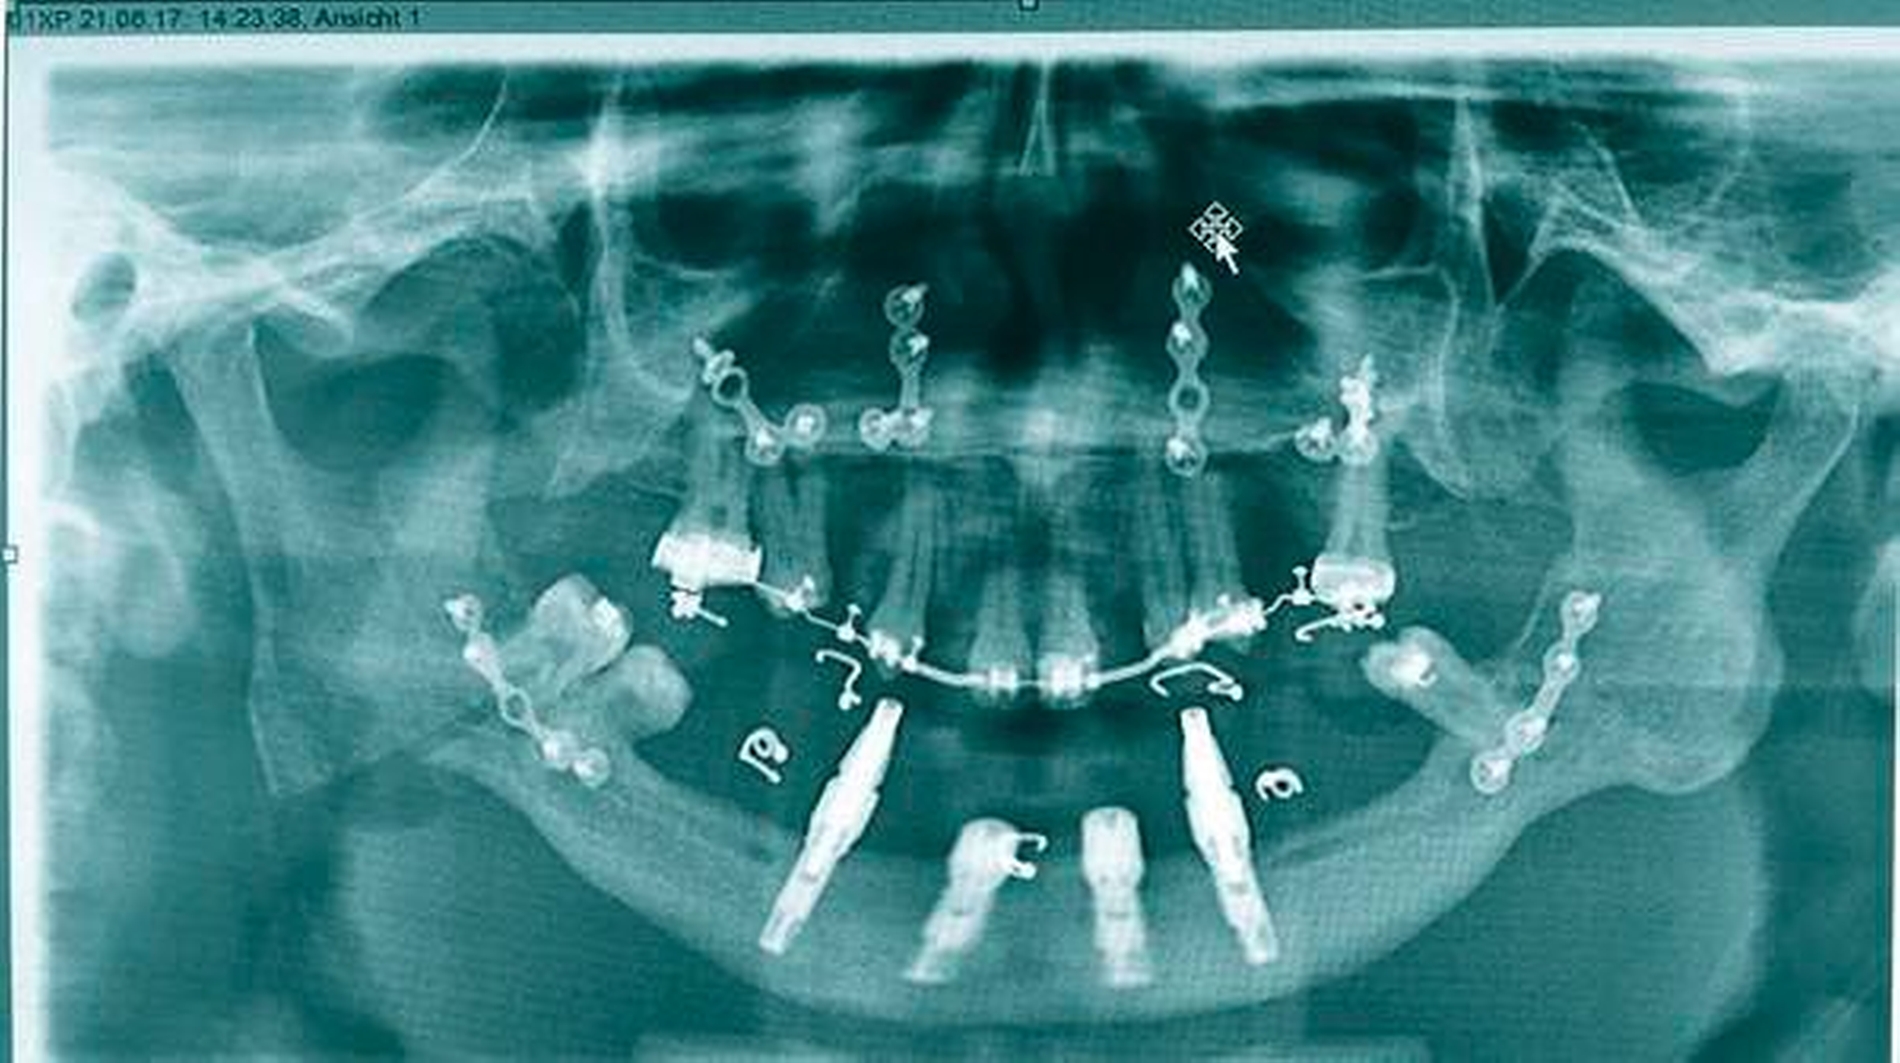

Anschließend wurde eine bimaxilläre Umstellungsoperation (in der Le-Fort-I-Ebene und nach Obwegeser/Dal Pont) durchgeführt (Abbildung 5). Hierfür wurde für den OP-Splint eine provisorische Implantat-getragene Prothese im Unterkiefer angefertigt, so dass die Implantate letztlich auch zur Eingliederung des OP-Splints dienten (Abbildungen 6 und 7). Zusätzlich konnte postoperativ durch die Implantat-getragene Prothese die Okklusion gesichert und das Risiko eines Rezidivs im Sinne einer Okklusionsverschiebung minimiert werden [Ohba et al., 2015].